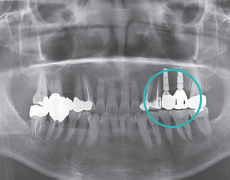

STEP 2

Primary Procedure (Fixture Placement)Place fixture in a proper site.

STEP 3

Secondary Procedure (Confirm osseointegration)Connect fixture and abutment.